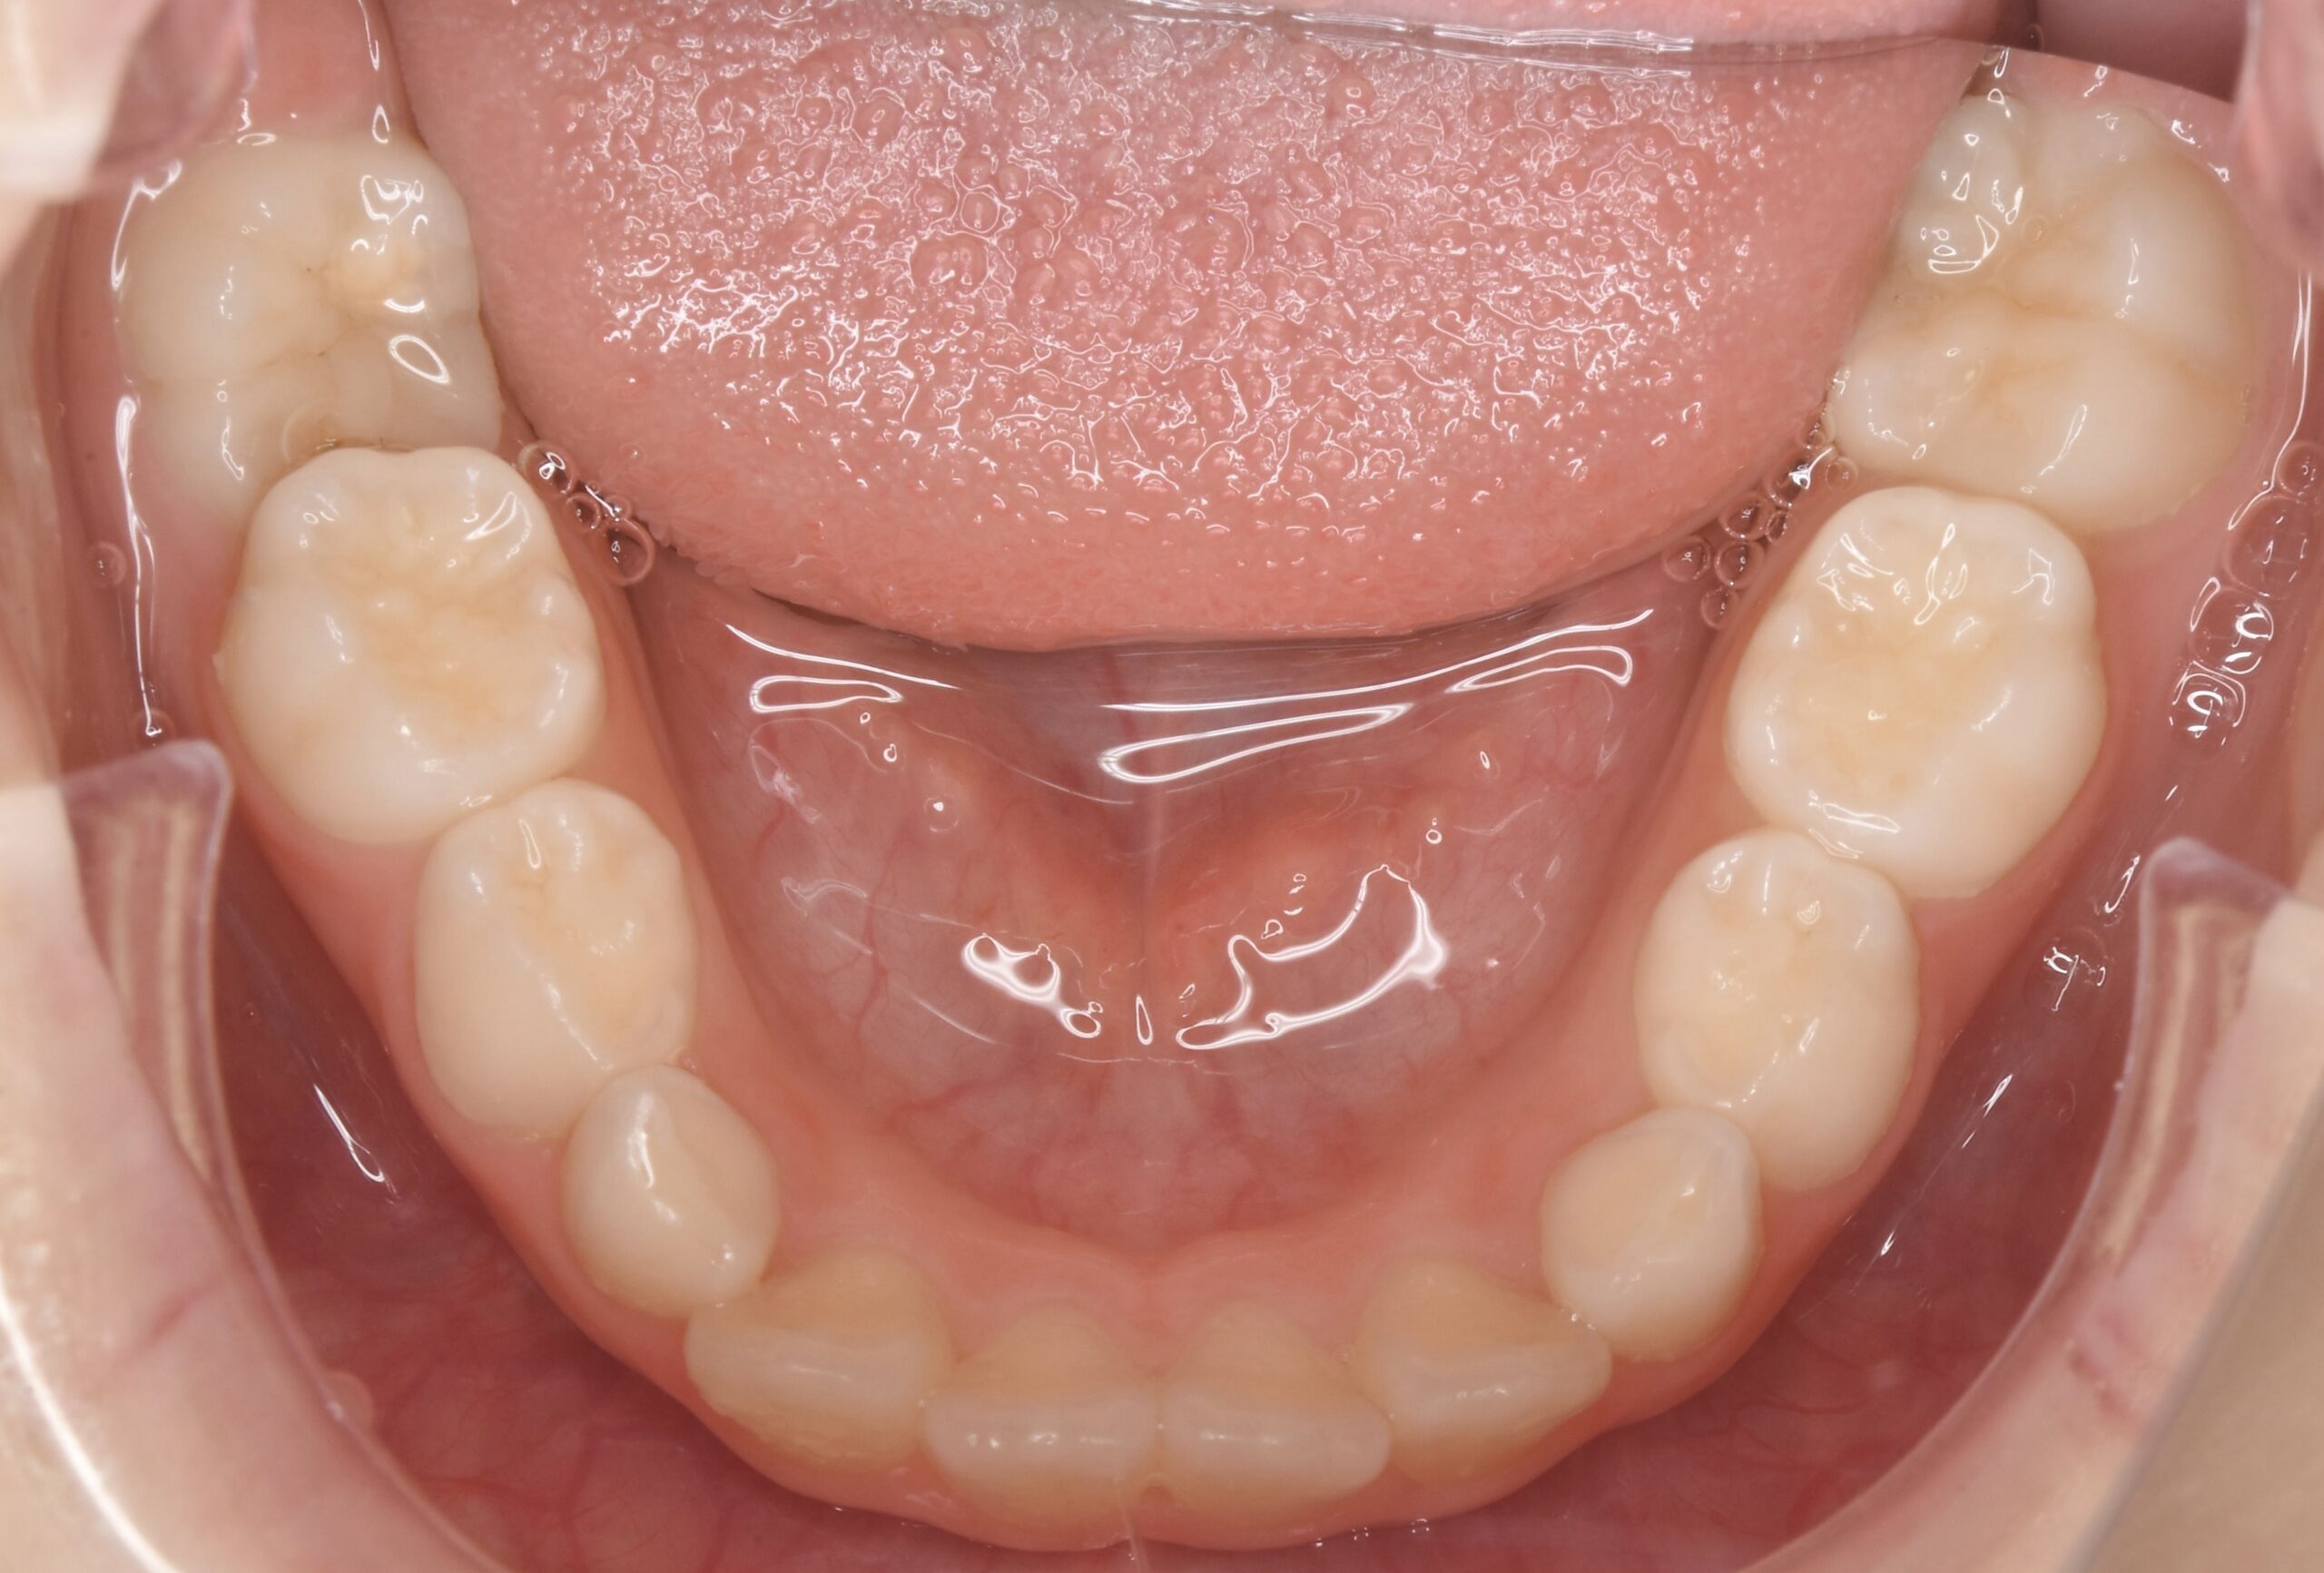

- BEFORE

| 治療内容 | 永久歯がきれいに並ぶスペースが不足していたため、上あごの成長を促す顎顔面矯正装置(拡大装置)を使用しました。 現在、第2大臼歯の萌出経過を観察中です。 永久歯の生え変わりに合わせて歯並びや噛み合わせを確認しながら、必要に応じて継続的な管理を行っています。 false |

| 使用装置 | 顎顔面矯正装置(拡大装置) false |